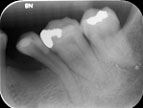

Chụp XQ kiểm tra sau khi hàn ống tủy